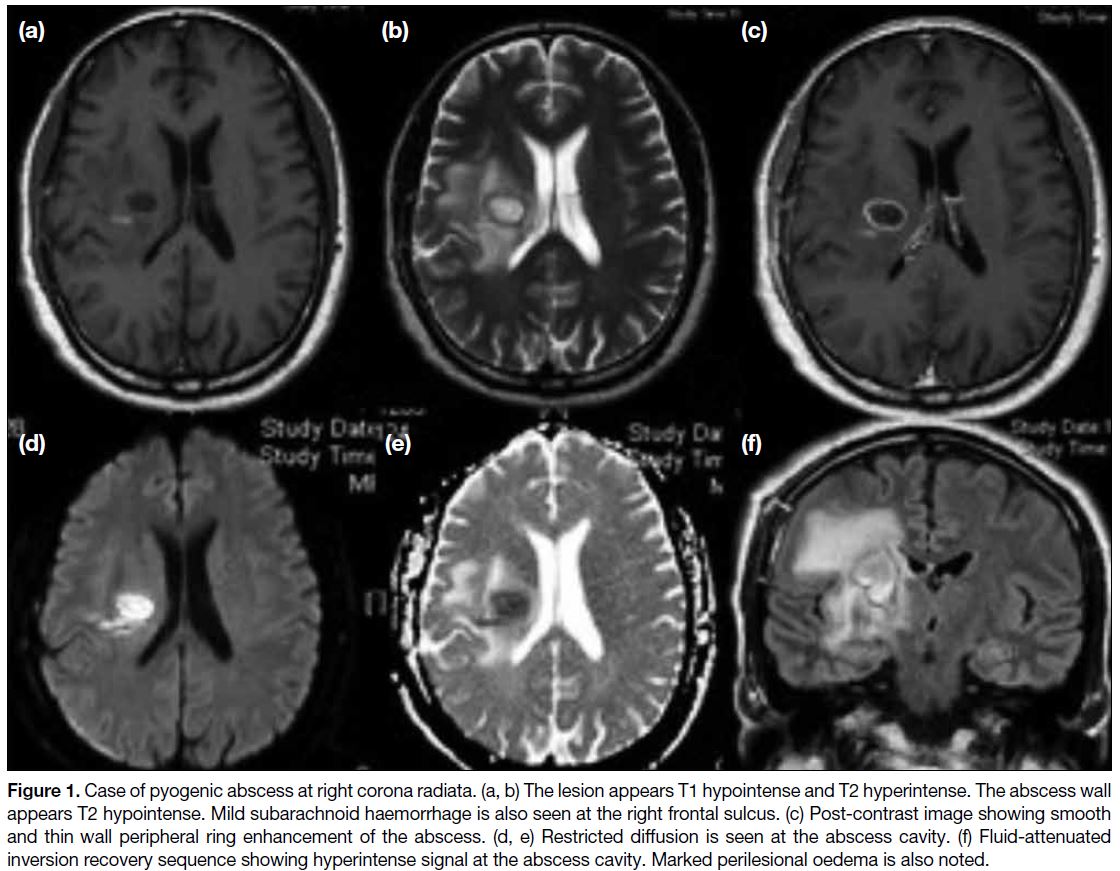

* **Imaging (CT/MRI)**: Ring-enhancing lesion, central necrosis (pus), surrounding edema. DWI: Restricted diffusion (key).

> * **Neurocysticercosis** (*T. solium*): **Ring-enhancing lesions with scolex**.

> * **Brain abscess**: **Ring-enhancing lesions**; *Streptococci*, *Staphylococci*.